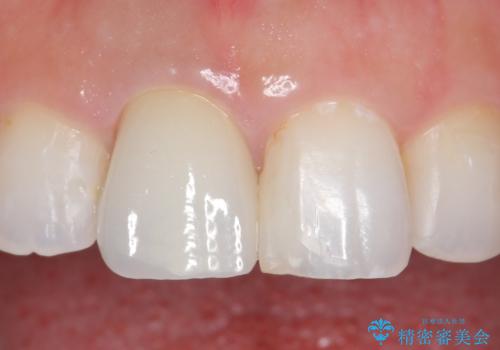

- 右上1の前歯の見た目が気になるので被せ物をやり替えたいといらっしゃった方の症例です。

再根管治療終了後、オールセラミッククラウン(スペシャル)によって隣在歯に合わせた補綴を行いました。

前歯の補綴ではオールセラミッククラウンを希望される患者様が多いですが、オールセラミッククラウンの中でも、エコノミー、スタンダード、スペシャル、エクセレントとランクがあります。

その中でも特に審美性が高いのがスペシャル、エクセレントです。スペシャル、エクセレントは口腔内写真をもとに熟練の技工士が、患者様の口腔内に合わせたオーダーメイドのクラウンを製作致します。